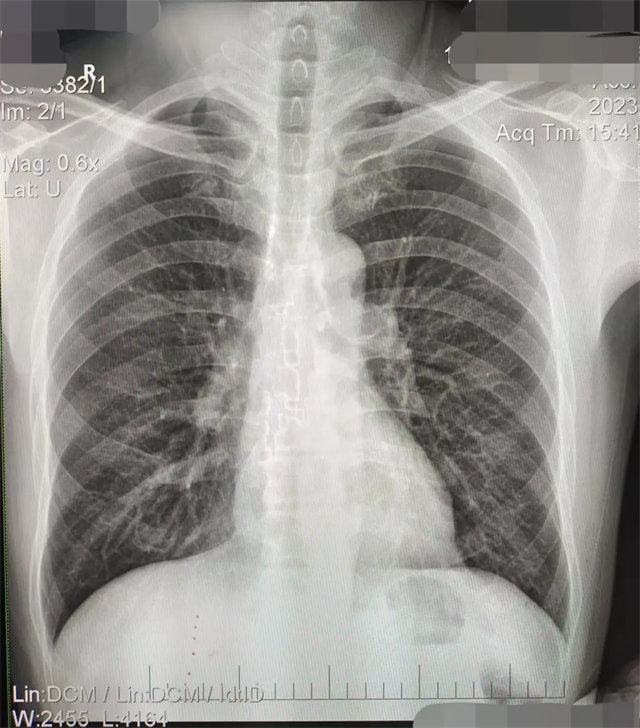

缺陷:左肩胛骨部分與左肺野重疊。

解決:使患者左肩旋前緊貼成像件重新曝光。